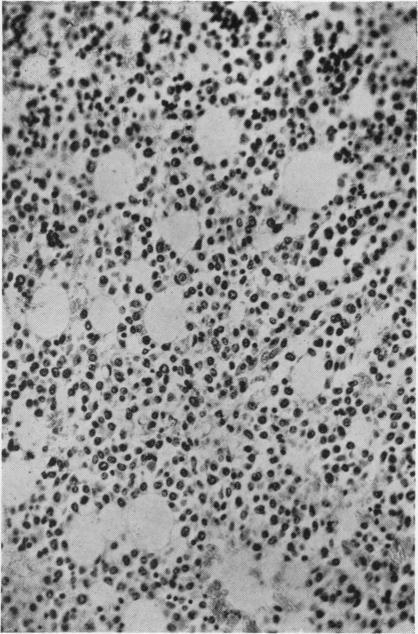

Two cases are presented in which aplastic anaemia was associated with thymus tumours. In Case 1 the patient had a pancytopenic aplastic anaemia and was treated with A.C.T.H. The marrow showed regeneration at necropsy. The thymoma in this case was unusual as there was thymic regression with fat replacement which may have been related to A.C.T.H. Case 2 was initially of a pure red cell anaemia with but little tendency to produce a leucocytosis in response to infection and was found at necropsy to have a lymphoepithelioma of the thymus. Previously reported cases are reviewed and the role of A.C.T.H. in treatment is discussed.

本文报告两例再生障碍性贫血合并胸腺瘤的病例。病例1患者患有全血细胞减少性再生障碍性贫血,接受促肾上腺皮质激素(ACTH)治疗。尸检时骨髓显示有再生迹象。该病例中的胸腺瘤较为特殊,存在胸腺萎缩伴脂肪替代,这可能与ACTH治疗有关。病例2最初表现为纯红细胞贫血,对感染几乎没有产生白细胞增多的倾向,尸检发现患有胸腺淋巴上皮瘤。对先前报道的病例进行了回顾,并讨论了ACTH在治疗中的作用。